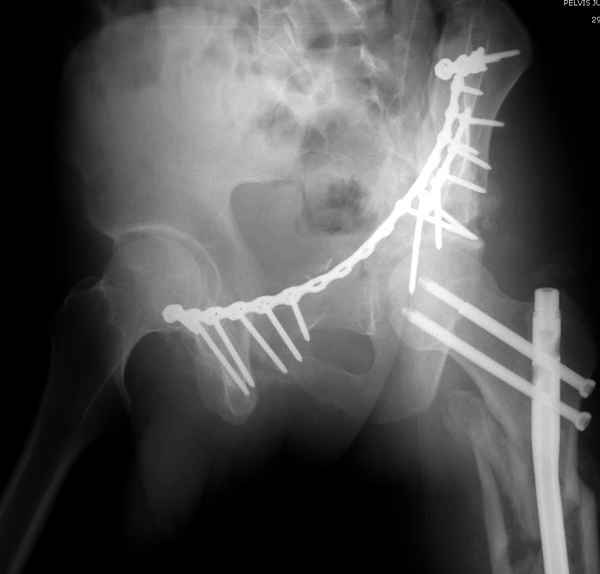

Здесь несколько вариантов двухколонных свежих переломов, которые были оперированы из одного-заднего, а также из двух: переднего и заднего доступов.

Имя     : 4 Bothcolumn postop.jpg

Тип     : image/jpeg

Имя     : 5 Bothcolumn postop 2.jpg

Имя     : 6 Bothcolumn postop 3.jpg